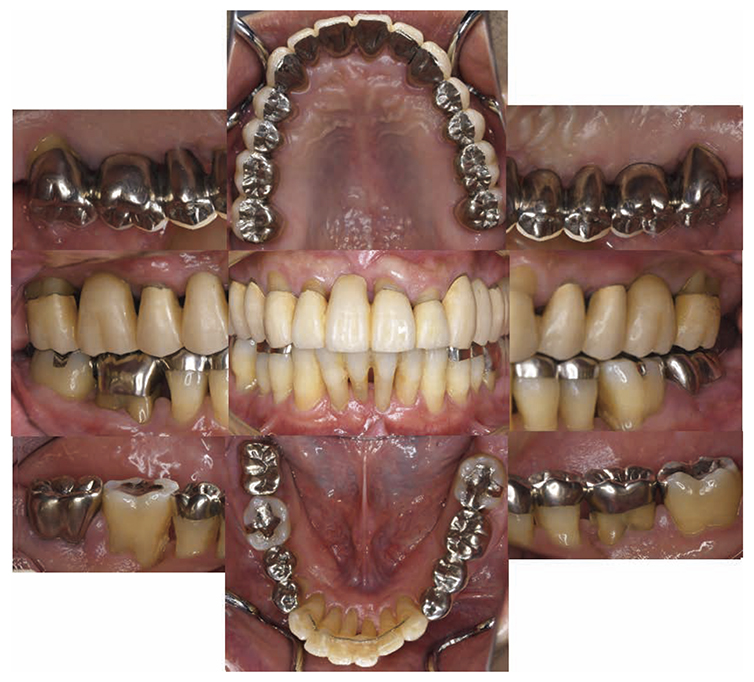

7) Reevaluation testing (December 2003)

At the reevaluation examination after treatment to restore oral function, the color of gingiva was pink, and with prosthetics, intraoral harmony was replicated esthetically and functionally. (Fig.6a). The average PD across the entire jaw was 2.1mm, maximum PD was 4.0mm, the ratio of PD of 3mm or below was 99.3%, no BOP was found and the condition of the periodontal tissue was stable (Fig.6b). In the X-ray, continuity of the alveolar hard line was replicated and the sequence of bone trabeculae was normal, and therefore, the patient transitioned to the SPT phase (Fig.6c).

Fig 6a

(Fig.6a) Intraoral photo after completion of restoration of oral function was completed(2013.4)

(Fig.6c) Digital X-ray 14 after completion of restoration of oral function (April 2013)

8)SPT (December 2013 onward)

After transitioning to SPT, the patient brushed 4 times daily after every meal and before bedtime and has continued to use an interdental brush. PCR levels have been consistently in the 20% range. SPT , which primarily consists of instructions on brushing and dental surface cleaning, has been implemented every other month to present, and efforts are made to maintain and manage oral hygiene in the long term to ensure that plaque control is not insufficient. While minor discoloring is observed on the prosthetics, the color of the gingiva is salmon pink and a macroscopically healthy appearance has been sustained (Fig.7a) . The average PD on the entire jaw is 2.1mm,maximum PD is 4.0mm,the ratio of PD of 3mm or less is 99.3%. No BOP has been found and the condition of the periodontal tissue has been stable (Fig.7b). In the X-ray, continuity of the alveolar hard line has been replicated and the sequence of the bone trabeculae has been normal (Fig.7c).